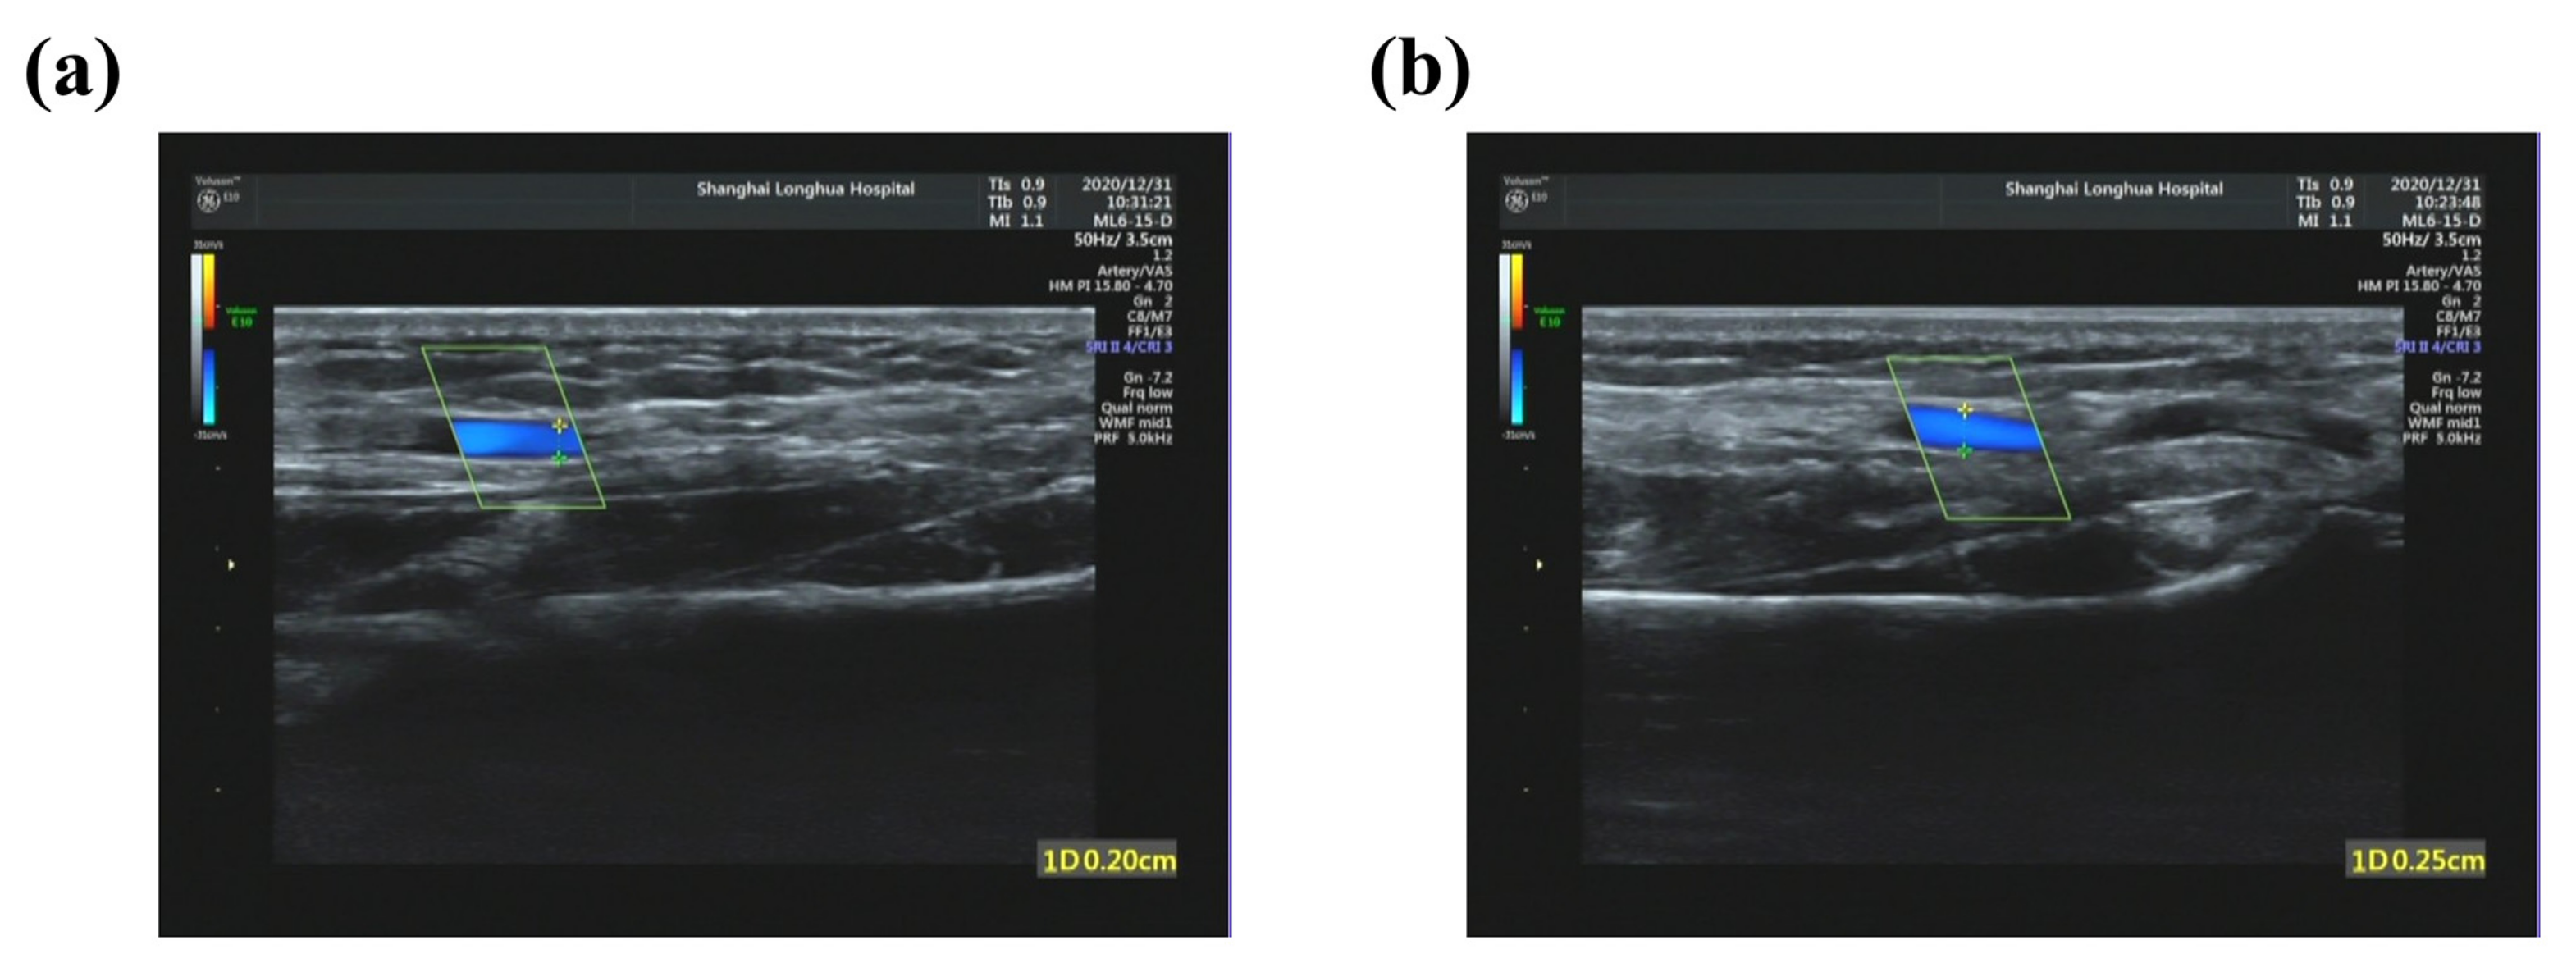

| Volunteer | Diastolic Diameter (cm) | Systolic Diameter (cm) | ΔD (cm) | Ds |

|---|---|---|---|---|

| 1 | 0.20 | 0.25 | 0.05 | 0.331 |

| 2 | 0.21 | 0.26 | 0.05 | 0.276 |

| 3 | 0.19 | 0.22 | 0.03 | 0.175 |